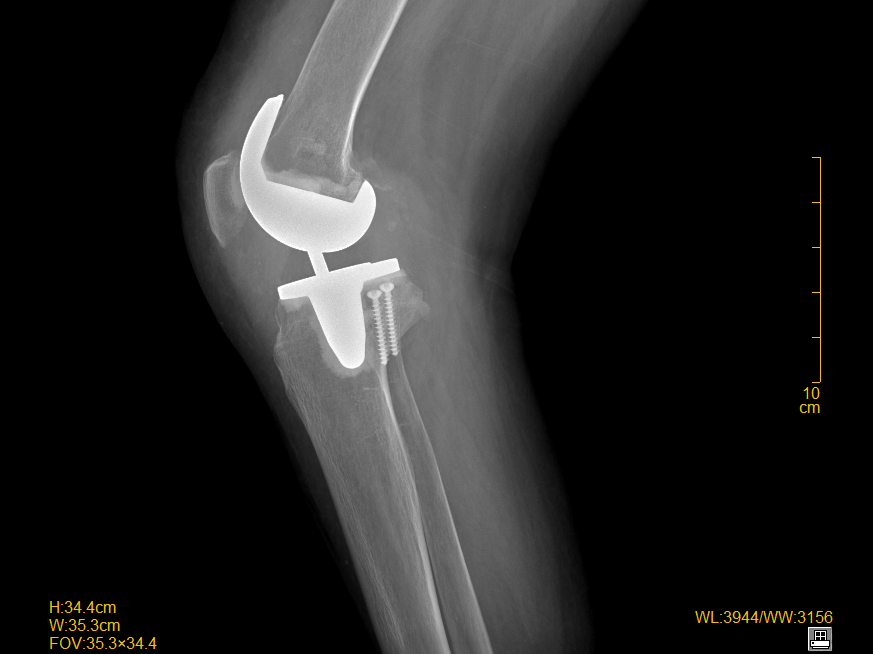

▲ 术后X线提示:关节位置良好,关节关系正常